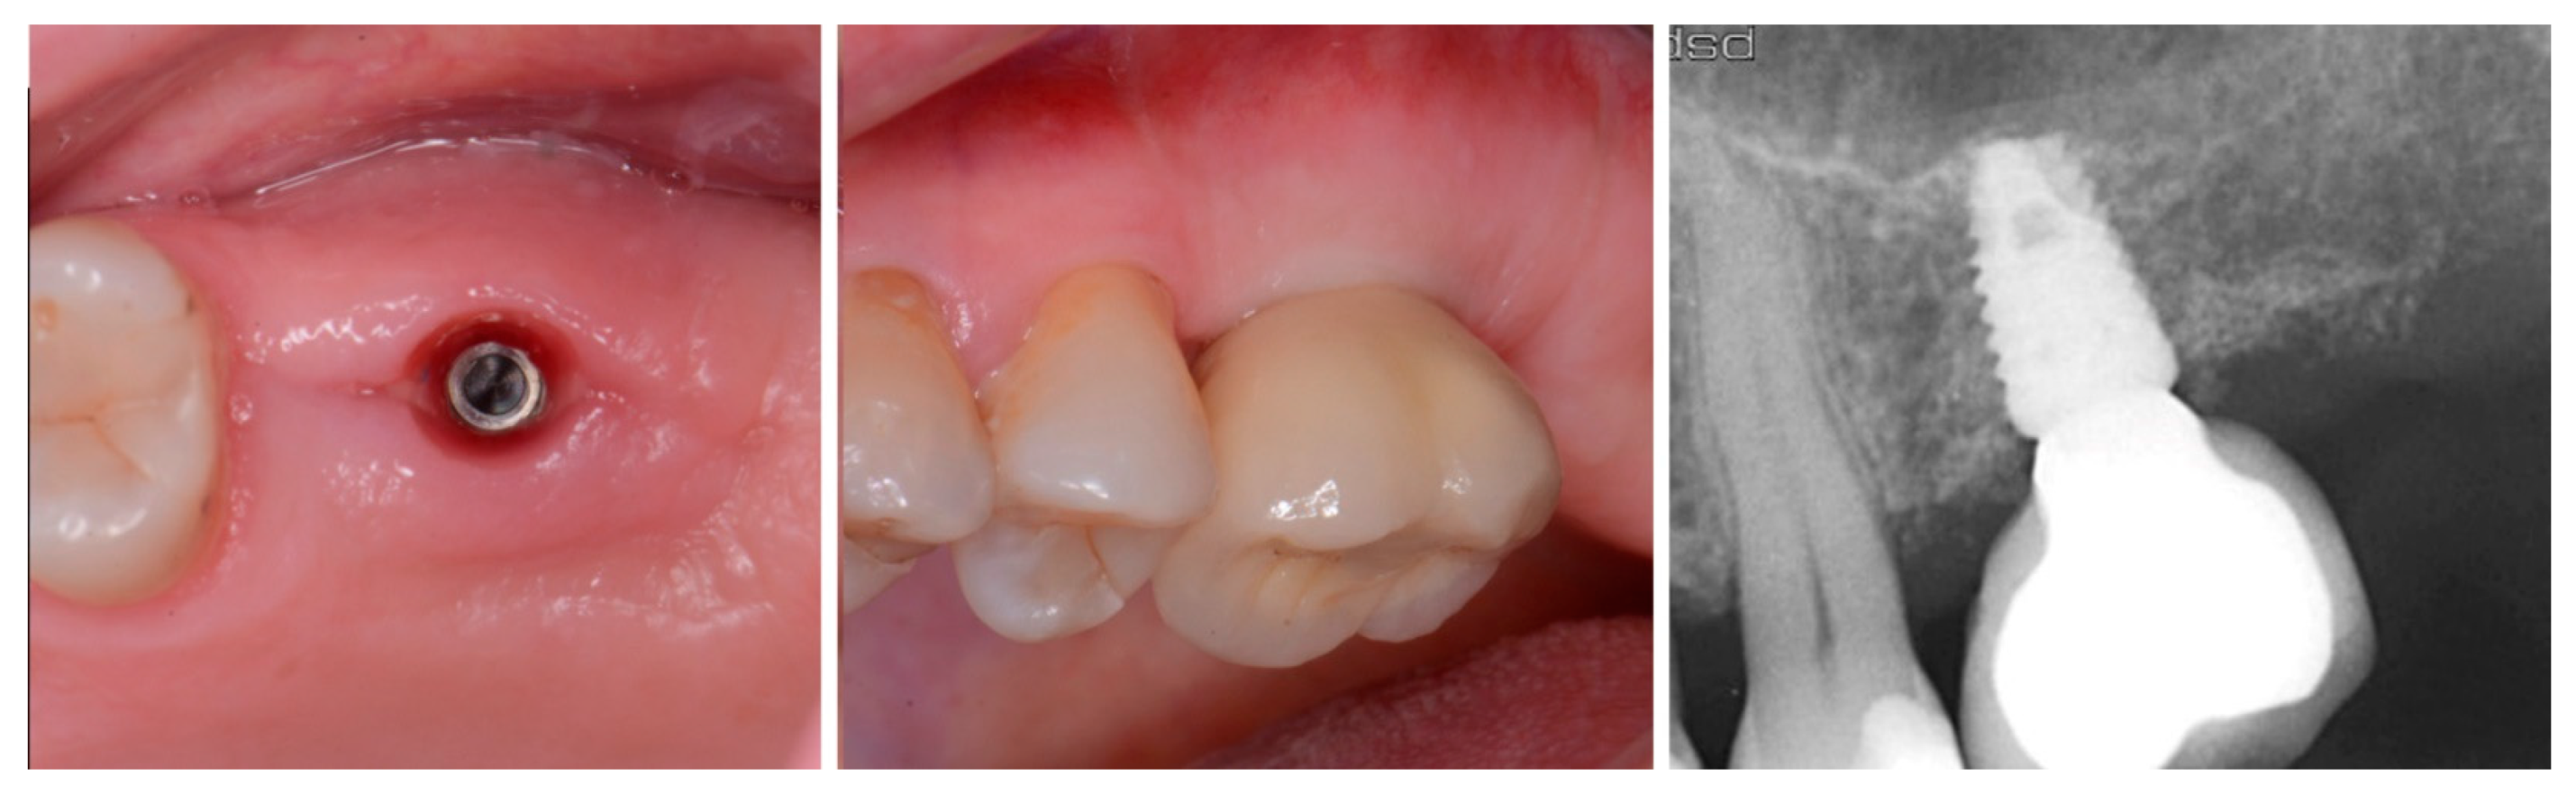

The patient returned at 10 weeks to initiate the restoration of the integrated implant. The implant was exposed, and the cover screw was removed (Figure 6, left). An impression was obtained, and a healing abutment was placed on the site while the restoration was fabricated at the laboratory. Following return of the restoration from the lab, the patient presented. The healing abutment was removed, and a screw-retained restoration was inserted and the screw torque was adjusted to the manufacturer’s recommendation (Figure 6, middle). A periapical radiograph was obtained to verify the seating of the restoration and graft incorporation with the surrounding host bone (Figure 6, right).

Figure 6.

Exposure of the integrated implant after 10 weeks of healing (left). Screw-retained restoration placement (middle) and a radiograph to document seating of the restoration at the implant connector demonstrating conversion of the graft material to host bone (right).